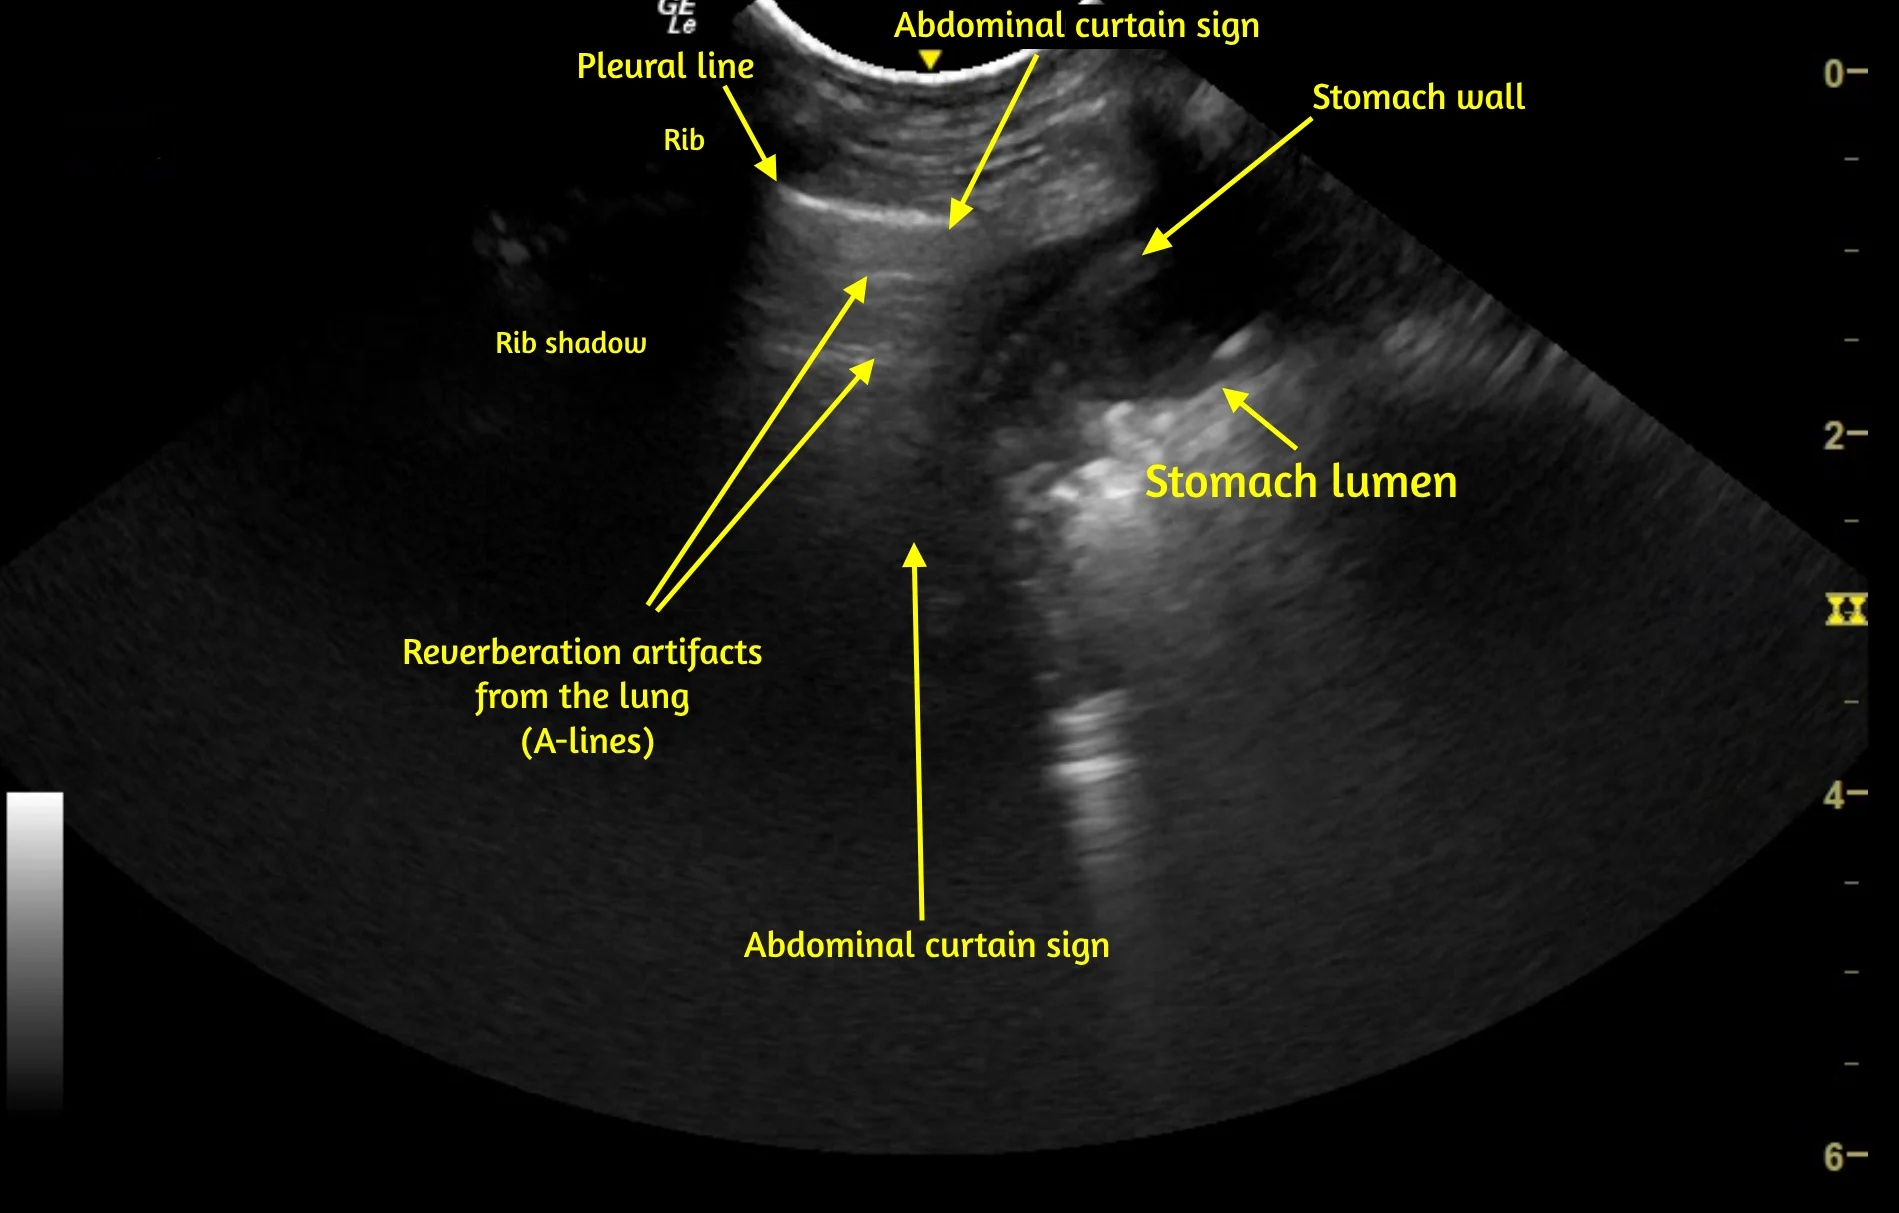

Familiarity with normal sonoanatomy, machine functions, image optimization, and sonographic artifacts that can result in false-positive or false-negative POCUS findings is also important. For example, abdominal structures below the caudal ribs can be confused with lung or pleural space pathology (Video 1), and rib or GI gas shadowing can obscure underlying structures, including pathology.

VIDEO 1 Pleural space and lung POCUS shows the left caudal lung border between the lung and abdomen. The vertical line (caudal lung border) that shifts cranially and caudally with respirations is the abdominal curtain sign. Caudal to the curtain sign, a small amount of liver is visible within the abdomen, followed by the stomach wall and gas and ingesta within the stomach lumen. The stomach wall can be misinterpreted as pleural effusion or stomach contents misinterpreted as lung consolidation if the operator is not familiar with the curtain sign. A labeled still image from the video is available below.